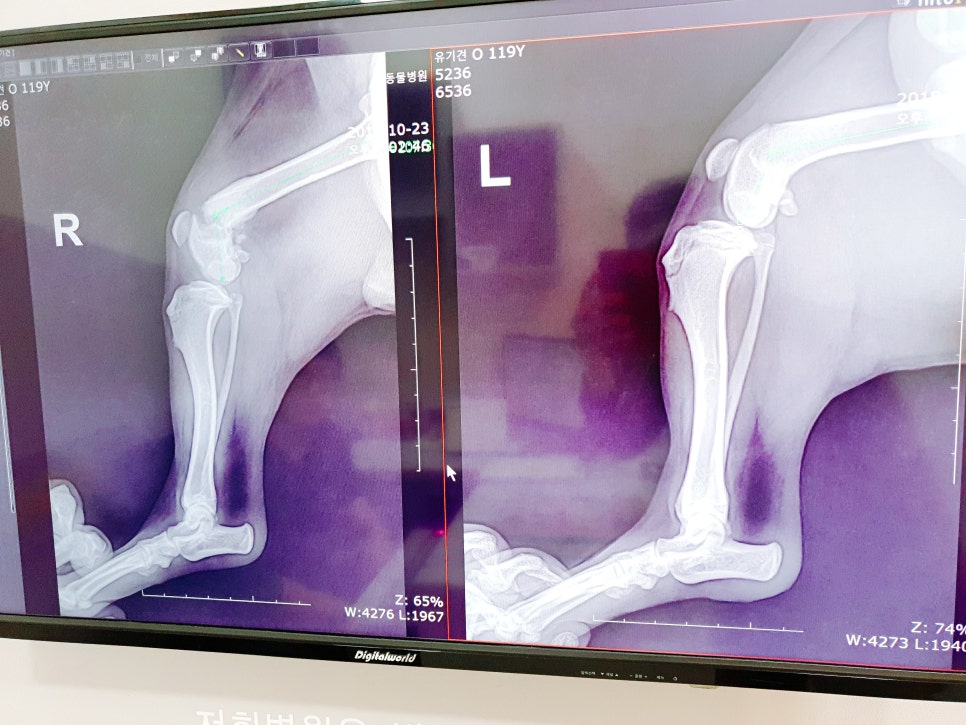

다리 엑스레이를 찍어 보니

아니나 다를까 뒷다리 오른쪽이

골절이 된상태로 적어도

골절후 2주 이상은

지난것 같다고 하더라고요

바로 골절이 된것을 치료하는 것과

시간이 지난 상태로 수술을 하는 것은

많은 차이가 있는데 이미 부러진 다리

뼈들이 제멋대로 붙어지고 있어서 그 뼈들을 다시

제자리를 잡고 맞추면서 수술을 한다고

하더라고요. 그래서 더욱 아프고 힘든 수술